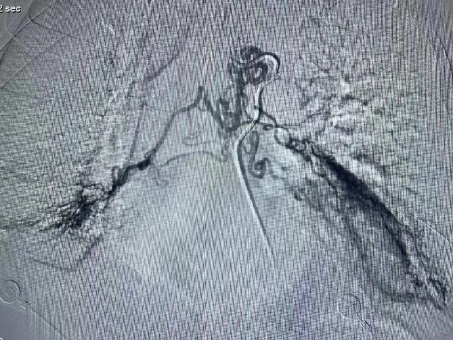

醫院呼吸內科團隊高(gāo)度重視患者的治療,組織全科人員討論(lùn)製定個性化治療方案,通過患者體動脈cta造影檢查,明確了包括支氣管動脈在內的5支病變血管。經充分術前準備,7月2日晚7點,曹辛瑜(yú)副主任在術中(zhōng)精準定位出血病變血管,及時用栓塞劑對病變血管逐個栓塞,完全阻斷病變血管(guǎn)血流,痰液立即恢複正常。患者手術(shù)順利,術後恢複良好。支氣(qì)管動脈栓塞術的應用,大大縮短患(huàn)者住(zhù)院時間,且有(yǒu)效降低患者出現大咯血窒息死亡風險。